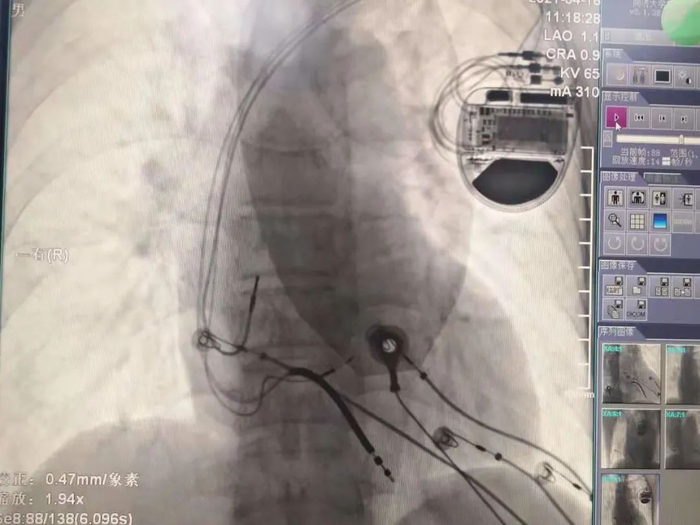

择日,孙冰主任医师和毛玉副主任医师所在的起搏团队为先生进行了起搏器植入手术。张先生植入的起搏器为三腔起搏器,共有三根导线经血管到达心脏,分别位于右心房、右心室和左束支。右心房、右心室得电极保证了心房心室收缩的同步性,并具有防治室速室颤的功能。而左束支电极可以纠正左束支传导阻滞,实现左室内部的收缩同步,改善心功能。经过精细定位和检测,左束支电极植入成功,起搏后可以看到张先生心电图的qrs波迅速变窄,标志左室收缩同步性的达峰时间和胸前导联qrs波移行也非常理想。手术很成功。术后心电图已经看不到原来宽宽的qrs波了,几乎与正常心电图完全一样。这意味着心脏电传导得到了改善,张先生的脸上也露出了笑容。

心脏起搏器